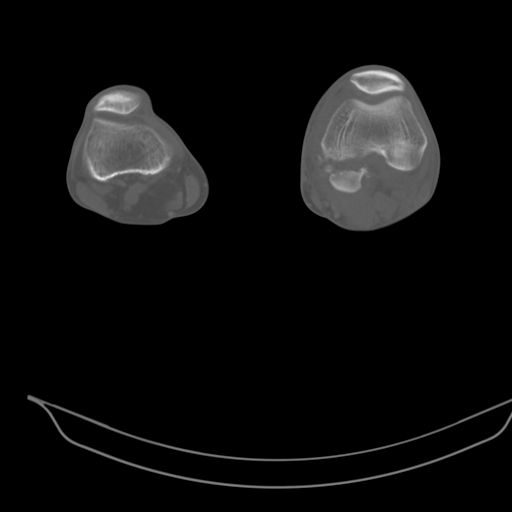

CT shows major bony fragments which are markedly rotated .With this amount of bony damage,you probably should attempt to get reasonably loooking knee with ORIF and thn if he needs a TKR due to pain a few years from now, then tleast you have something looking like a knee that you can replace rather than having to use revision knee for a primary TKR now. 4 weeks is not too long .what is the condition of soft tissues?

При внутрисуcтавных переломах трехмерные (3D) изображения, кроме красивого снимка, не дают полную информацию о состоянии отломков, самыми информативными являются корональные срезы на КТ и обычная длинная ренгенограмма конечности для сравнения оси конечности.

Фронтальные внутрисуставные переломы мыщельков бедра, так называемые Hoffa fracture, не частые, но встречающиеся переломы, в основном они связаны с травмой высокой энергией.

В зависимости от смещения рекомендуется сопоставление костных фрагментов с последующей жесткой фиксацией.

В вашем случае доступ будет медиальный, сопоставить развернутый медиальный мыщелок и фиксацию надо произвести в передне-заднем

направлении шурупами 4.5 мм в диаметре, углубив головку шурупов под хрящ, а поперечную фиксацию - межмыщелковыми шурупами. Желательно применить шурупы 6.3 мм в диаметре. Дополнительная Buttress technique пластина предотвратит перелом от скольжения.

Даже при сросшемся переломе мыщелка рекомендуется реконструктивная операция для предотвращения последующих варус или вальгус деформации.

Место образовавшего костного дефекта после разворота мышелка заполняется спонгиозной аутокостью. Костная пластика применяется даже

в свежем случае.